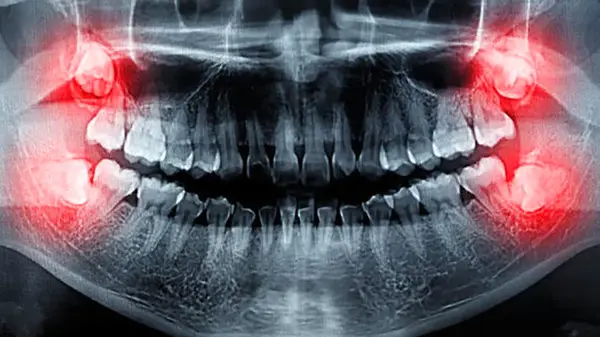

برای پیشگیری و درمان درد دندان عقل، روش های مختلفی وجود دارد. بررسی وضعیت دندانهای عقل با عکسبرداری، رعایت بهداشت دهان برای جلوگیری از عفونت و پوسیدگی ، مصرف داروهای مسکن برای کاهش درد و جراحی و کشیدن دندان عقل تحت نظر دندانپزشک از جمله راه های پیشگیری و درمان درد درمان عقل است.